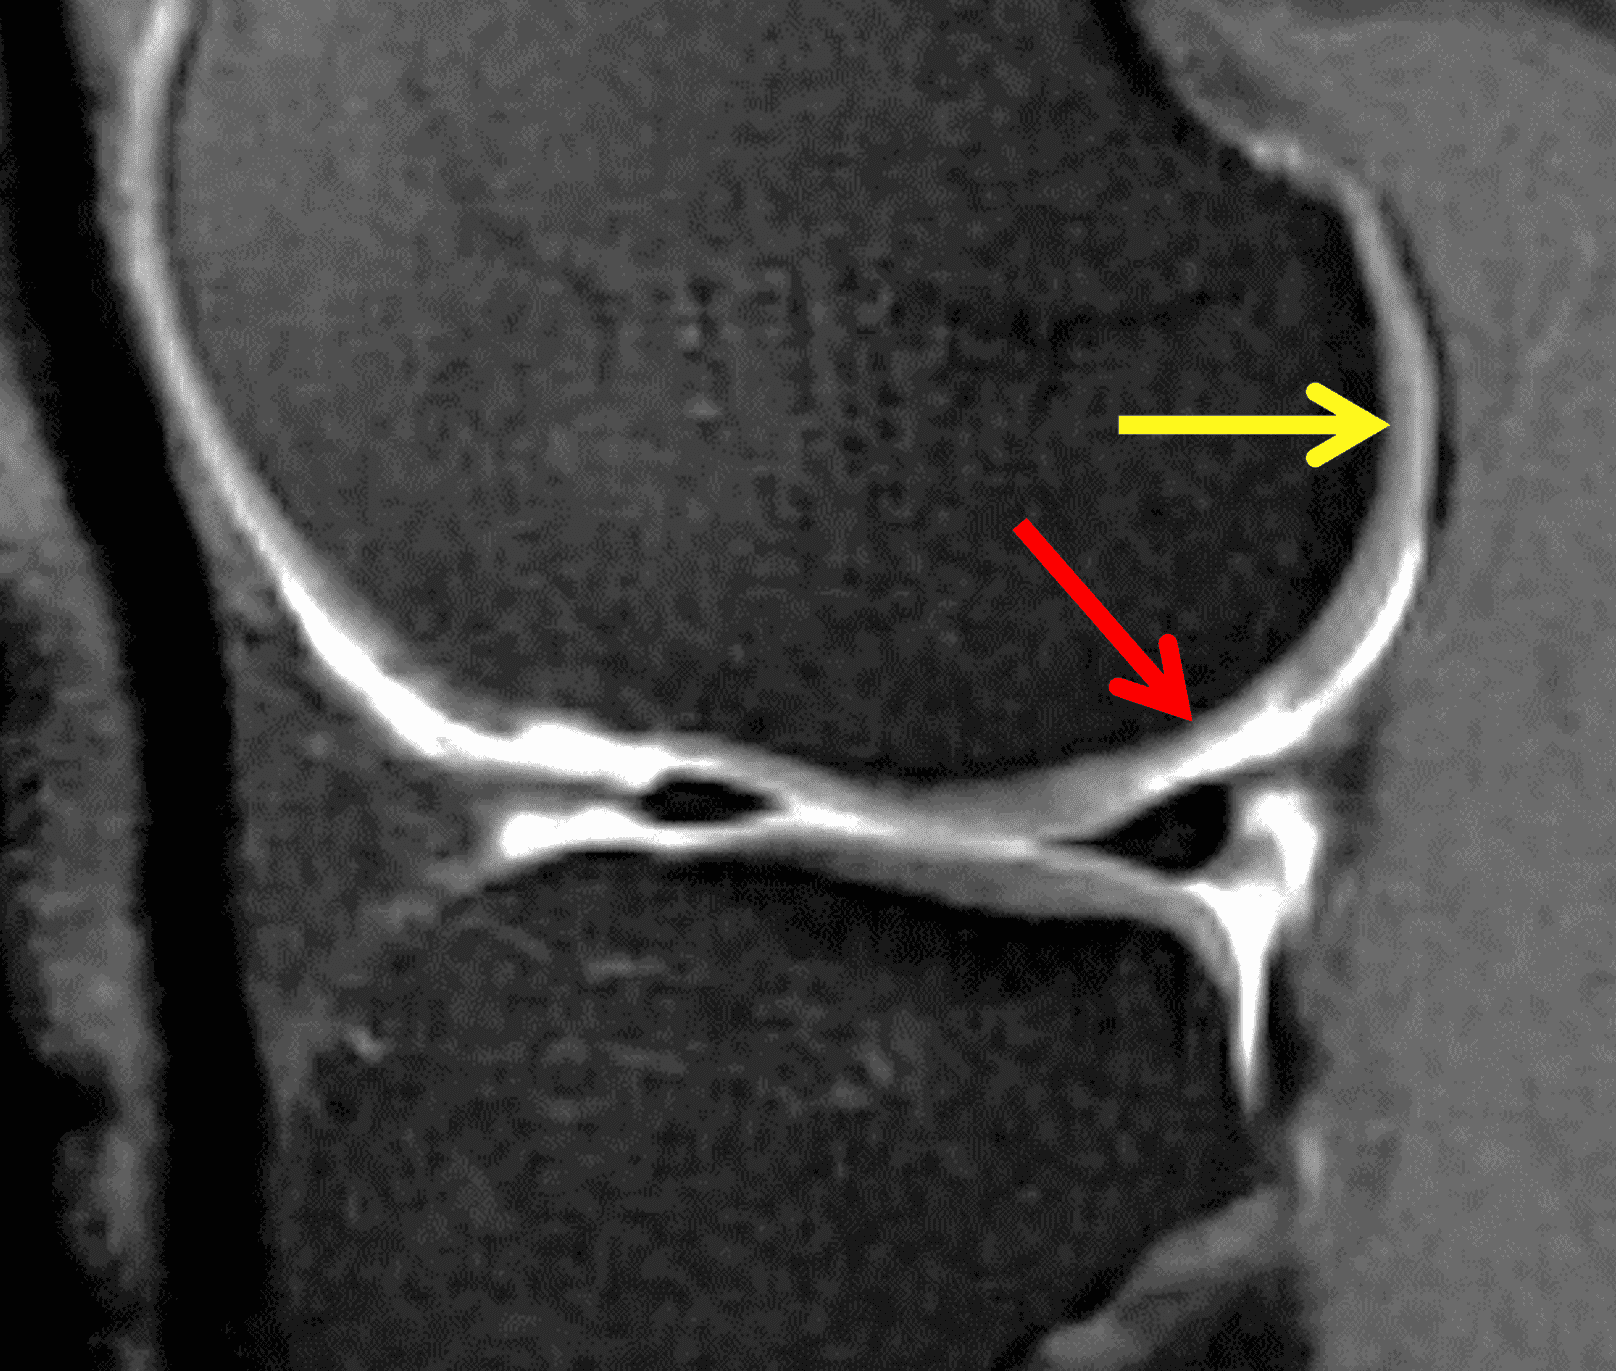

A 32-year-old man suffered a traumatic chondral injury to the medial femoral condyle that was treated with an osteochondral allograft 20 months previously. Representative images from a current knee MRI include (1A) coronal fat-suppressed fluid-sensitive and sagittal (1B) T1-weighted, (1C) proton density-weighted, and (1D) T2-weighted sequences. Are the post-operative MRI findings normal and expected, or abnormal and pathologic? Based on these images, would you characterize the procedure as a success or failure?

Figure 2: (2A) On the coronal image, the margins of the osteochondral graft are faintly visible (arrowheads). Both the graft and underlying bone show mild marrow edema, an expected finding. (2B) The T1-weighted image shows continuity of the marrow in the graft (asterisks) with the underlying bone, indicating osseous integration. A bioabsorbable pin (arrow) used for graft fixation is partly visible. (2C) The proton density-weighted image shows a low signal intensity seam (black arrow) between the native cartilage and transplant, as well as a defect in the subchondral bone plate of the graft (red arrow) where the pin was drilled, both normal findings. (2D) The T2-weighted image shows a smooth, congruent articular surface (arrows), restoring the normal anatomy, and a tiny subchondral cyst. No findings are present to suggest graft failure. The patient’s current symptoms were attributed to pathology elsewhere in the joint (not shown).

Successful osteochondral allograft procedure.

The postoperative imaging appearance of osteochondral allografts is similar to autografts (Figure 2).33 The subchondral bone plate of the donor and recipient sites do not have to match, but the articular surface should be congruent. Grafts that fail to incorporate by one year have a poor prognosis. Persistent marrow edema (beyond 12 months), a thick graft interface containing cysts or fluid, and subsidence of the graft are associated with poor osseous healing and worse outcomes. Extensive host marrow edema and severe synovitis may be a clue to immunologic rejection of the graft (Figure 18).21, 34